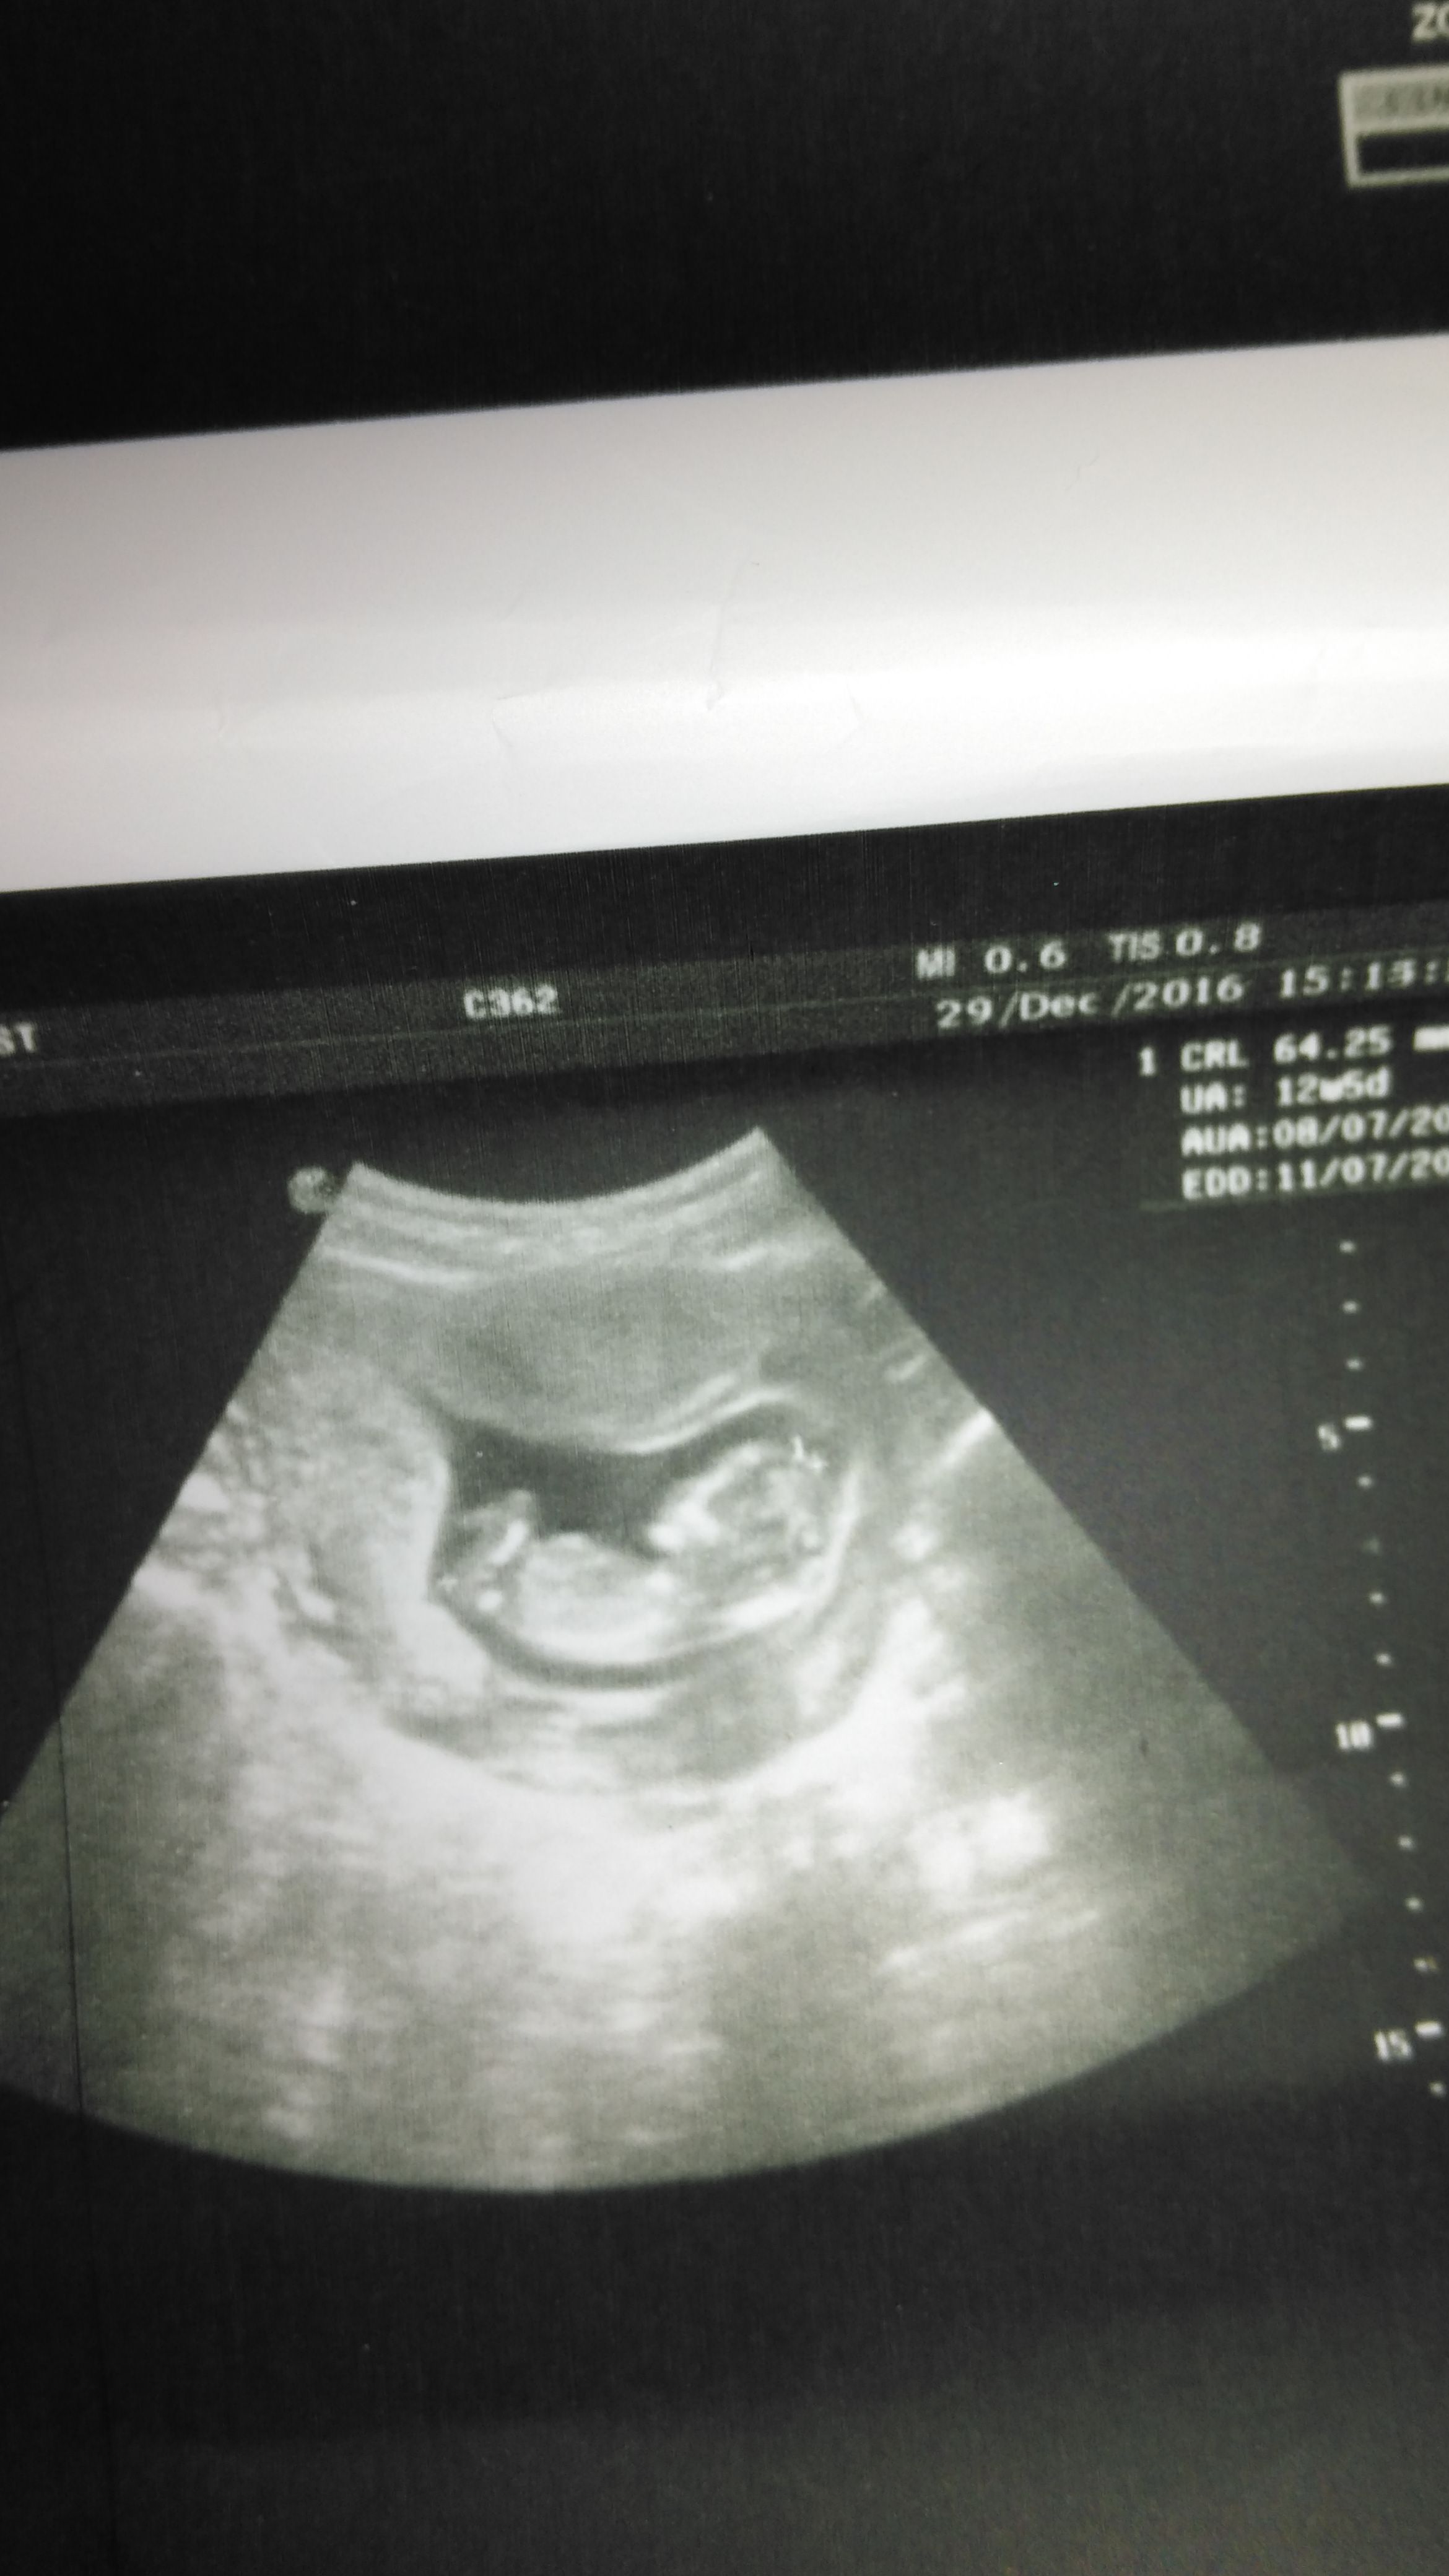

S Sedatunc Yeni Üye Üye 7 Ocak 2017 #118 Lutfenn benimkine de bakar misiniz. Simdiden tesekkur ederim Moderatör tarafında düzenlendi: 8 Ocak 2017

Sevimli cadı Daimi Üye Üye 8 Ocak 2017 #119 Sedatunc' Alıntı: Lutfenn benimkine de bakar misiniz. Simdiden tesekkur ederim Ekli dosyayı görüntüle 73279 Ekli dosyayı görüntüle 73280 Genişletmek için tıkla ... Sizin resimler net değil yorumlayamam malesef

Sedatunc' Alıntı: Lutfenn benimkine de bakar misiniz. Simdiden tesekkur ederim Ekli dosyayı görüntüle 73279 Ekli dosyayı görüntüle 73280 Genişletmek için tıkla ... Sizin resimler net değil yorumlayamam malesef